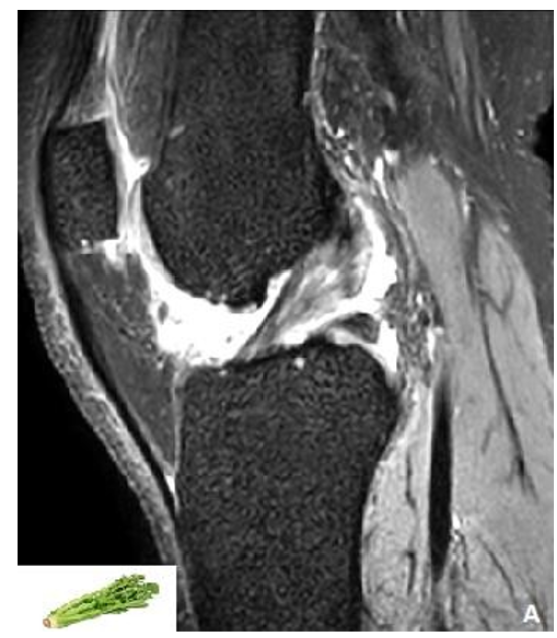

Unraveling the Celery Branch Sign: Understanding Mucoid Degeneration of the Anterior Cruciate Ligament

Hajar Zebbakh, Yassine Zerhari, Hatim Essaber, Asaad El Bakkari, Soukaina Allioui, Hounayda Jerguigue, Youssef Omor and Rachid Latib. 14(5): 27-29.